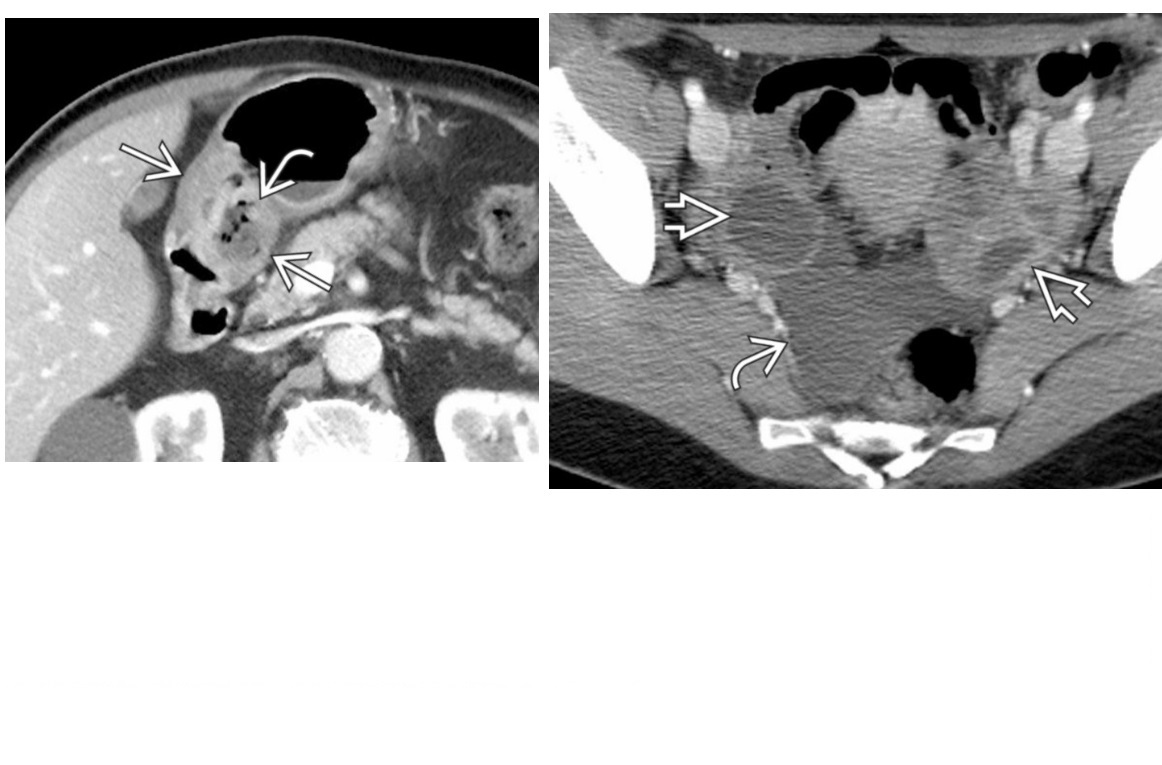

CT enterography features of active Crohn’s disease

**mucosal hyperenhancement **- most sensitive indicator but seen in other bowel diseases most specific sign for chrons - **Prominence of the vasa recta adjacent to the inflamed loop of bowel (comb sign) along with increased mesenteric fat attenuation** wall thickening (thickness >3 mm) CT enterography to depict extra-enteric disease/complications including -obstruction -sinus tract -fistula and abscess formation long-standing/inactive features include -submucosal fat deposition -pseudosacculation -surrounding fibro-fatty proliferation -fibrotic strictures MR enterography and enteroclysis - MR enteroclysis was superior to MR enterography in demonstrating mucosal abnormalities. -MR enteroclysis better bowel distension but not necessarily better diagnostics -MR enterography is more acceptable to the patient than MR enteroclysis